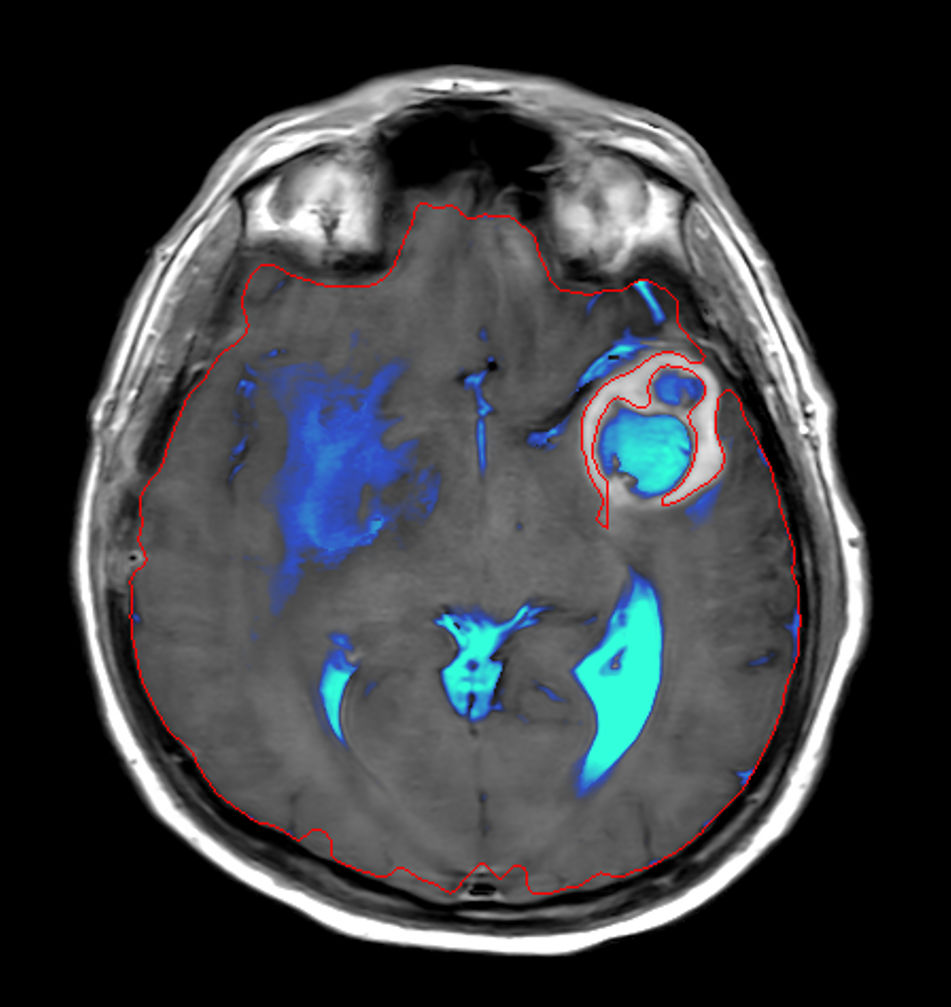

3D T1w TFE (Axial reformat)Post-Gado

3D T1w TFE (Coronal reformat)Post-Gado